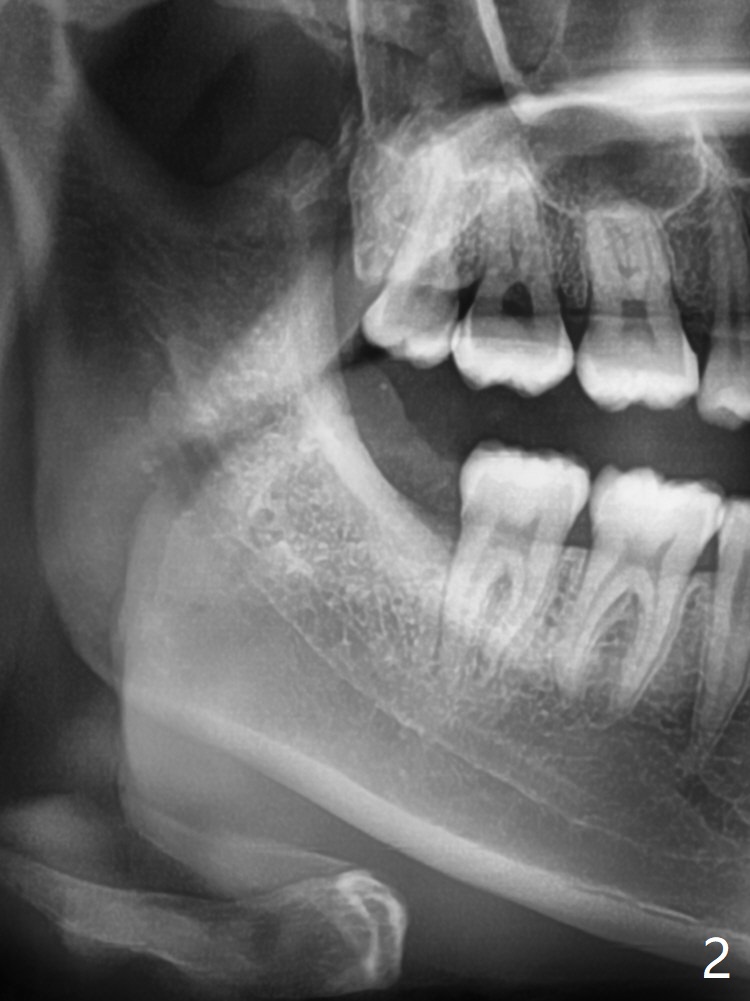

Fused Apices

A 22-year-old woman presents to clinic for #32 extraction at the recommendation of her grandmother (ex-dentist, Fig.1). It is difficult to anesthetize the tooth, which needs to be sectioned multiple times, including to split the roots. To prevent dry socket Osteogen plug is placed, followed by 4-0 plain gut suture.